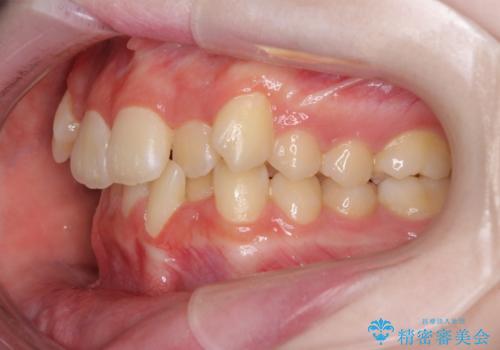

- 上下前歯のデコボコを気にして来院された患者様です。

前歯の叢生は強かったのですが、口元が引っ込んでいる印象であったため、非抜歯にて矯正治療を行うこととしました。